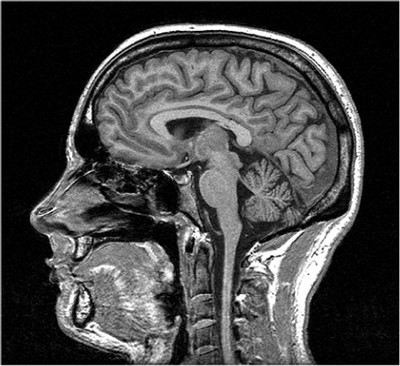

What diagnostic technique does this image depict?

MRI